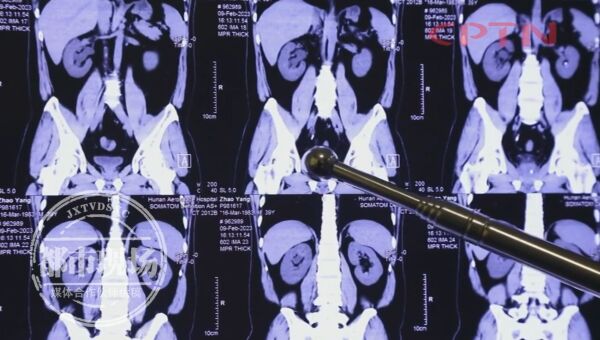

赵先生患结石已经多年,前几年结石不大,没发作过,所以他也没当回事。今年检查后,发现肾脏、输尿管内都有结石,并且还造成了尿路梗阻,他也感受到了不可言喻的疼痛。他猜测,导致这结石屡屡“找上门”的,正是他最爱的可乐。

目前,经过“无创输尿管软镜取石术”后,赵先生体内的结石已经清除干净。而对于可乐是否会导致结石,长沙南湖医院结石中心陈健教授也给予了分析。